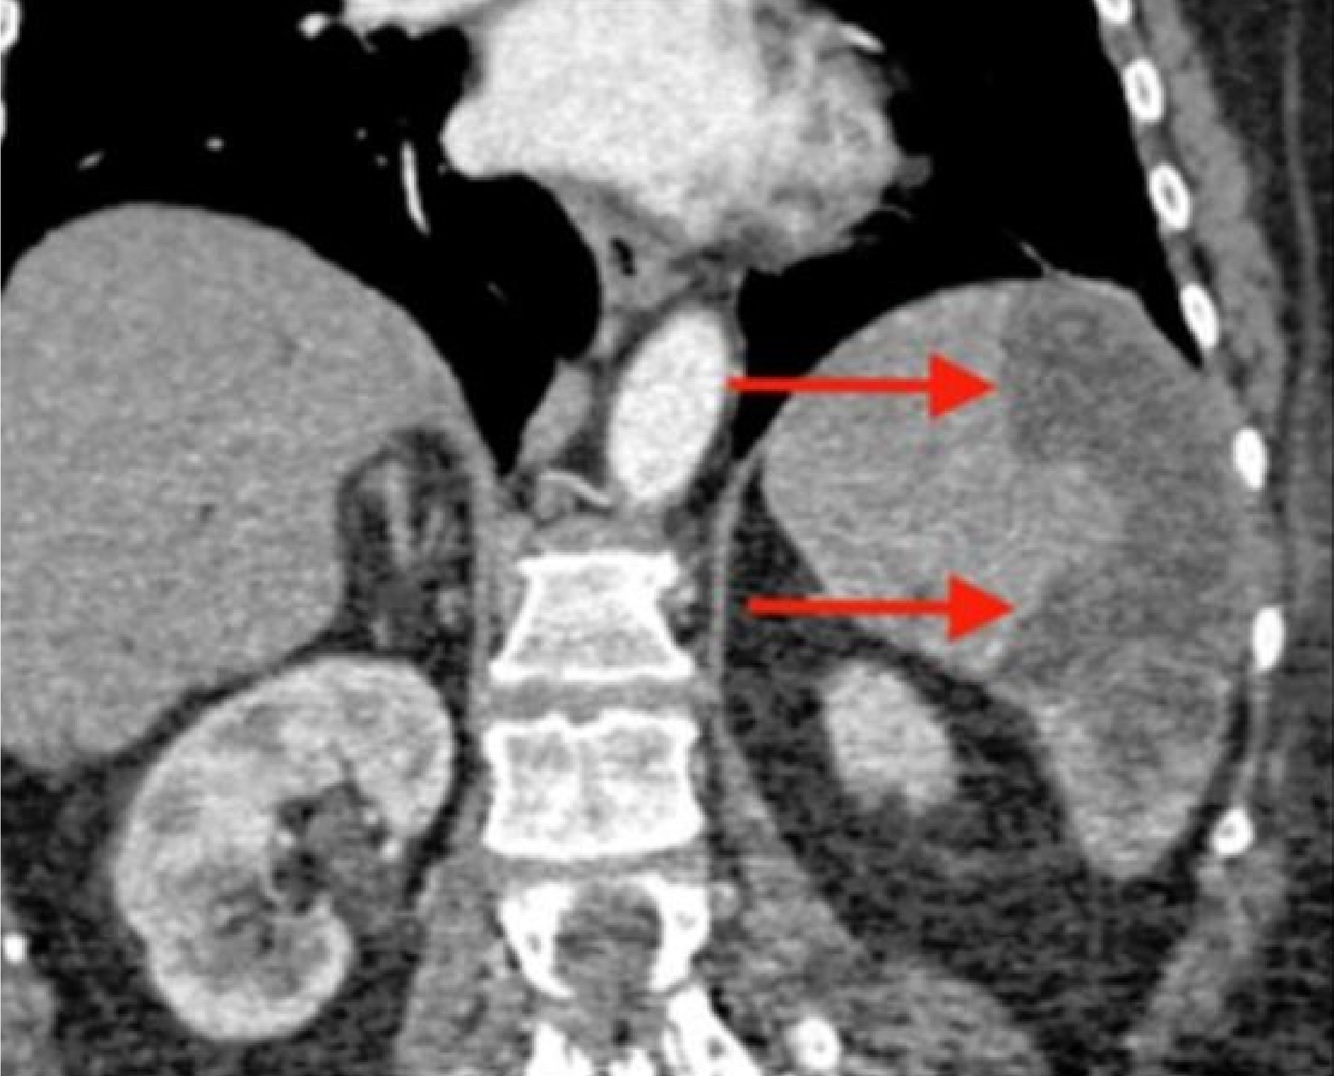

splenic infarct:

The image on the left demonstrates an enlarged spleen